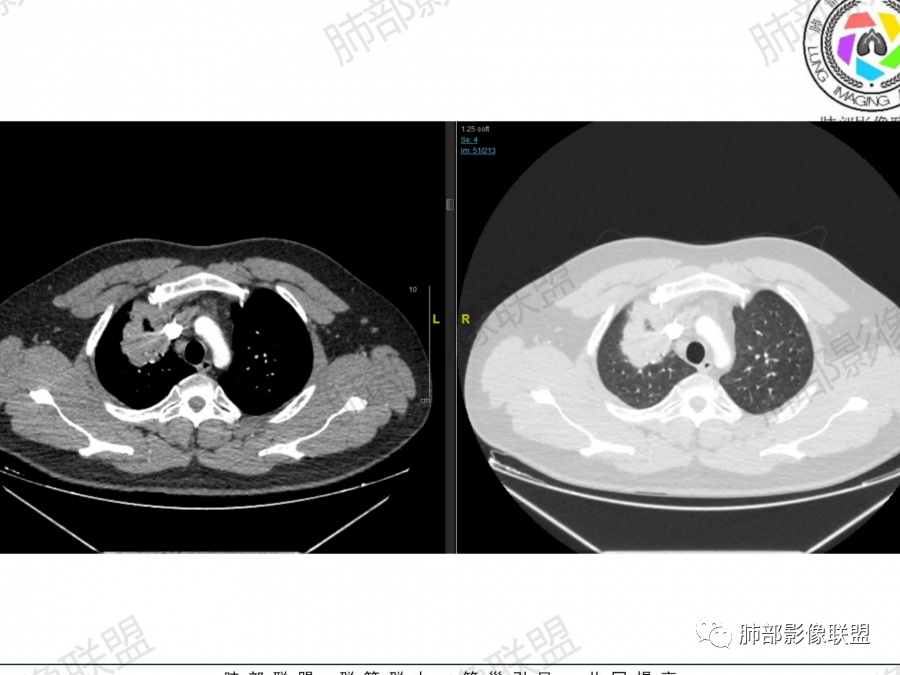

中年男性,咳嗽气喘一个月,血象不高,双肺野多发肿块,右肺上叶,右肺下叶胸膜下,近脊柱旁,肿块有膨隆有收缩,似多结节融合,内有多发小空泡,边缘似有晕,支气管进入走形比较自然,血管进入,走形自然,支气管阻塞不明显,考虑感染性病变,隐球菌可能,鉴别血管炎。

晨读,青年男性,咳嗽气喘病史,铁蛋白及D2聚体升高,右肺多发病灶,上叶团块影,深分叶,不均匀强化,可见血管征,支气管充气征,走形自然。右肺下叶背段球形阴影,有融合趋势,可见空洞,洞壁光滑,有血管自然通过,下叶外侧段靠近胸膜球形阴影,有血管进入,总体恶性证据多,淋巴瘤首选。

青中年男性患者,咳嗽、气喘1月,铁蛋白增高,抗组蛋白抗体及D二聚体增高,胸部CT:右肺上叶尖段大片实变影,似乎有结节融合而成,边界清楚,内部见扩张的支气管及血管影,增强扫描轻度不均匀强化,右肺下叶见多发类似病灶,有沿支气管分布趋势,综合考虑感染性或炎性病变,首选结核,次选血管炎,鉴别淋巴瘤

晨读:男性,37岁,咳嗽、气喘1月,加重2天。胸部CT:右肺上叶尖段、右下叶胸膜下和支气管树周围多发结节影、大片实变(由多结节融合形成),部分边界较清、部分周围模糊晕,病灶内悬浮空泡、支气管充气征、部分支气管进入后堵塞,血管漂浮,密度较均匀,综合考虑:隐球?鉴别淋巴增殖类病变。